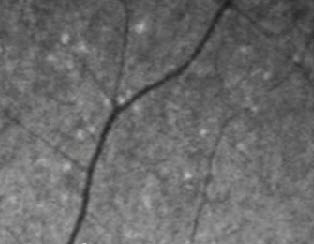

Noninvasive retinal imaging device detects Alzheimer’s 20 years in advance

Device could be FDA-approved by 2015 and early signs of Alzheimer’s could be detected in a regular ophthalmologist exam